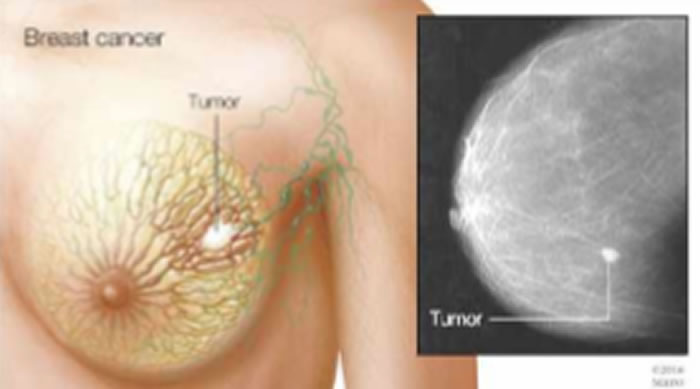

(神秘的地球uux.cn报道)据EurekAlert!:明尼苏达州罗切斯特 -- Mayo Clinic研究人员发现,一种用于治疗血癌的药物可能对治疗三阴性乳腺癌也有效果。 三阴性乳腺癌是最具攻击性和致命性的乳腺癌(breast cancer)之一。 该研究(study)发表在《临床研究杂志》(Journal of Clinical Investigation)上。

该研究发现,经美国食品和药物管理局批准用于治疗某些血液癌症的药物5-氮杂-2’-脱氧胞苷(地西他滨)可显著抑制三阴性乳腺癌(包括对化疗有抗性的肿瘤)的生长,这种反应取决于某种被称为DNA甲基转移酶蛋白的关键蛋白的存在,该蛋白仅存在于一部分三阴性乳腺癌中,而这提供了一种方法来确定哪些患者可以从该治疗中获益。